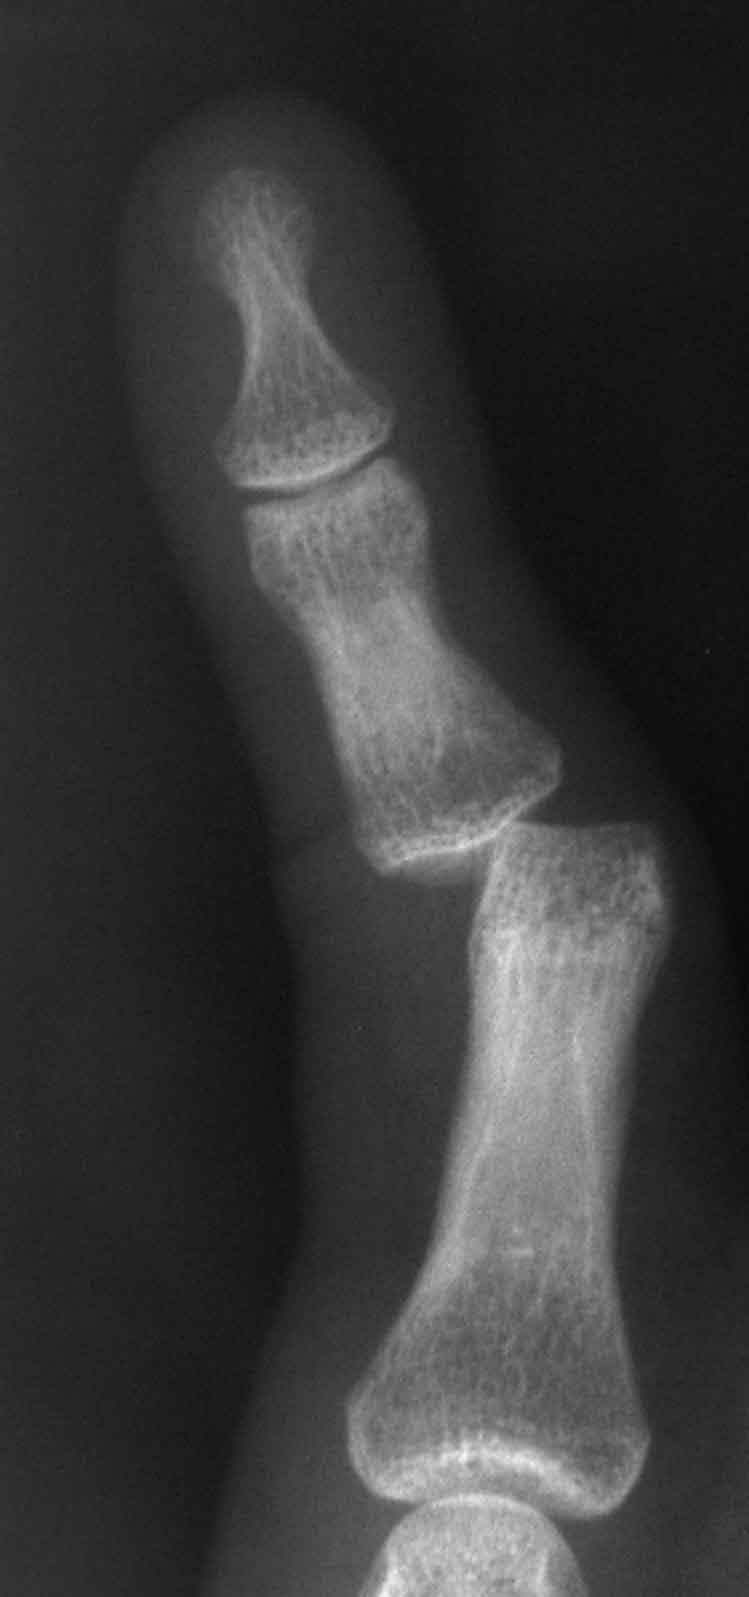

Proximal Interphalangeal Joint Dislocation Handipedia

from handipedia.yale.edu